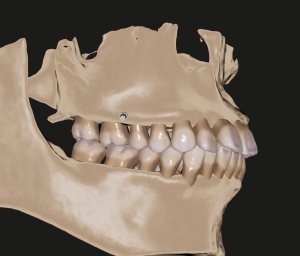

一人ひとりの歯列、顎骨の状態に合う理想的な咬合を作るためのシミュレーション、現実的な歯の移動限界の把握に利用したりしています。

(歯列と顎骨を連動させた状態。)

※スタッフの歯列、CTデータです。許可を得て、使わせていただきました。